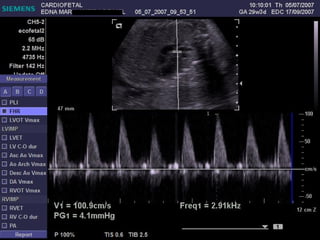

ECOCARDIOGRAFIA FETAL Modo B Modo M Doppler ¿CUANDO? A partir de la sem 12 por vía TV A partir de la sem 18 por vía abdominal Optimo: semana 22

Ritmo